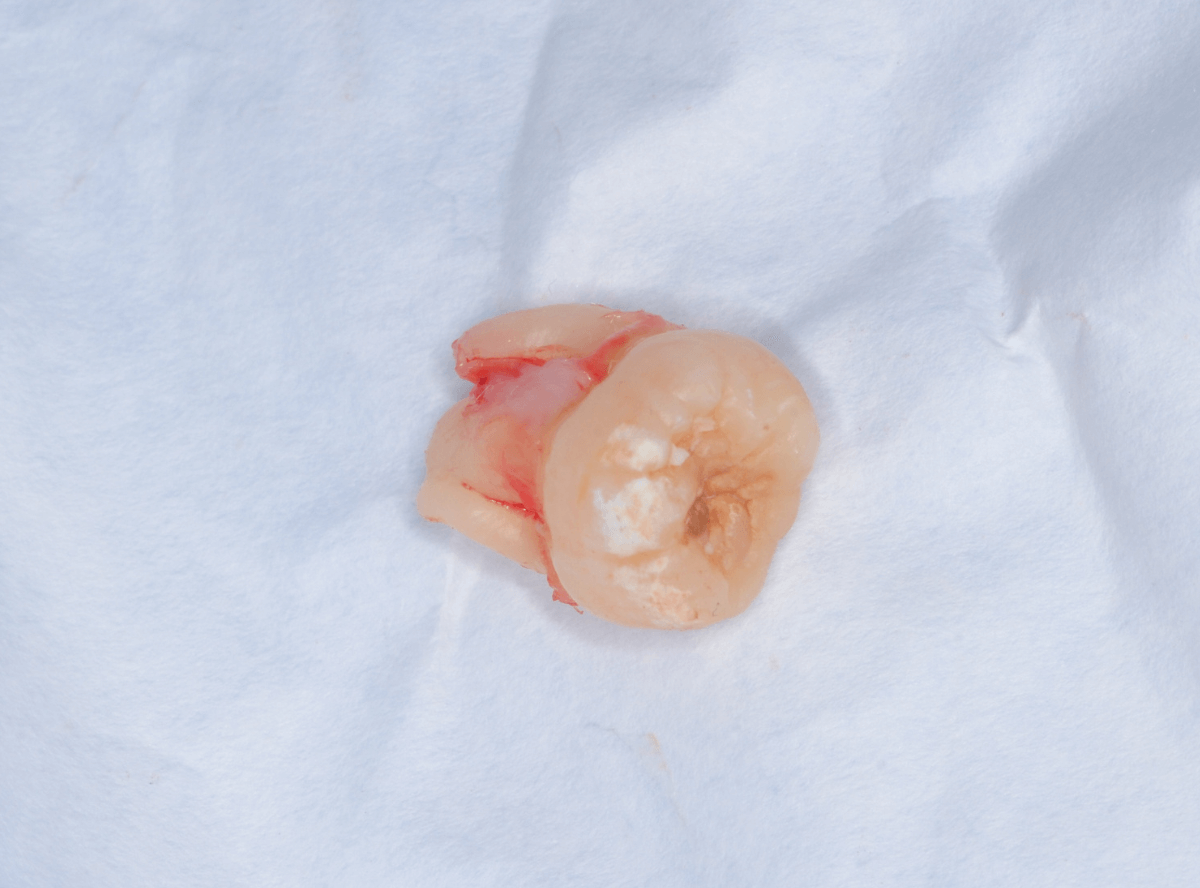

ここでは、比較的簡単なおやしらずの抜歯の例を中心にご紹介します。

このようなおやしらず、あなたはありませんか?